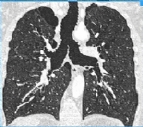

APP PARA INVESTIGAR NÓDULOS PULMONARES: FAÇA O DOWNLOAD

Em março de 2017, a Sociedade Fleischner - uma sociedade de radiologia torácica multidisciplinar - lançou uma atualização estabelecendo diretrizes revisadas para o manejo de nódulos pulmonares detectados incidentalmente em imagens de TC de ...